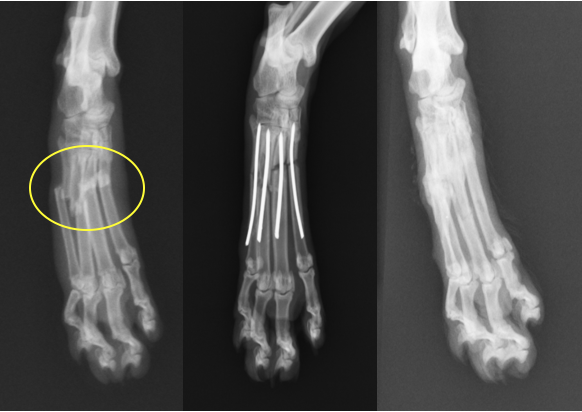

右第3指、第4指の骨折と左第3指の骨折です。それなりに髄腔が広いため太めのピンを入れています。